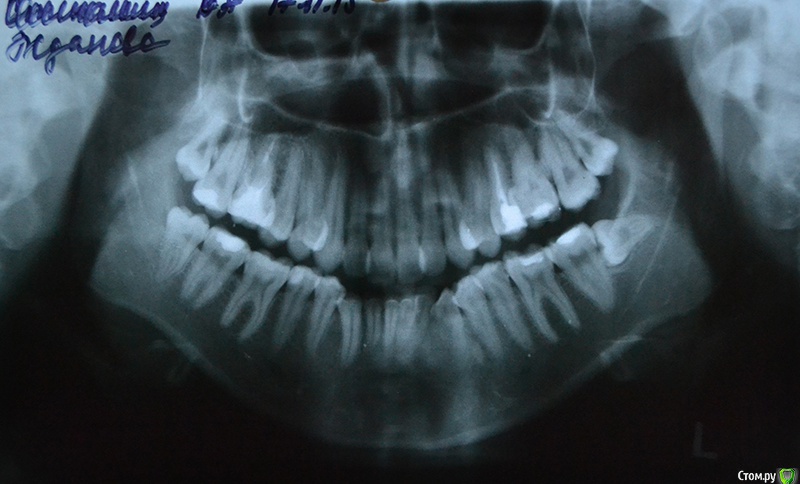

Мне 22 года, планирую исправить проблемы с прикусом, сейчас ищу информацию, рассматриваю варианты.

Очень нужен совет - действительно ли в моем случае лучшим выбором будет удаление 4ок на обеих челюстях?

Консультировалась у двух ортодонтов, оба сказали: без вариантов, зубы крупные, места не хватает.

Если все же удалять, то вопрос - обязательно ли по два на каждой челюсти? Я читала, что иногда удаляют и по одному, главная проблема в таком случае, вроде бы, это угроза асимметрии, но у меня она и без того очень заметна) Вопрос - может быть, если удалить по одному зубу с левой стороны, то будет легче как-то скорректировать асимметрию?

П.С. Само собой, я буду удалять лежащий на боку зуб мудрости) И правую нижнюю 8ку, скорее всего, тоже.